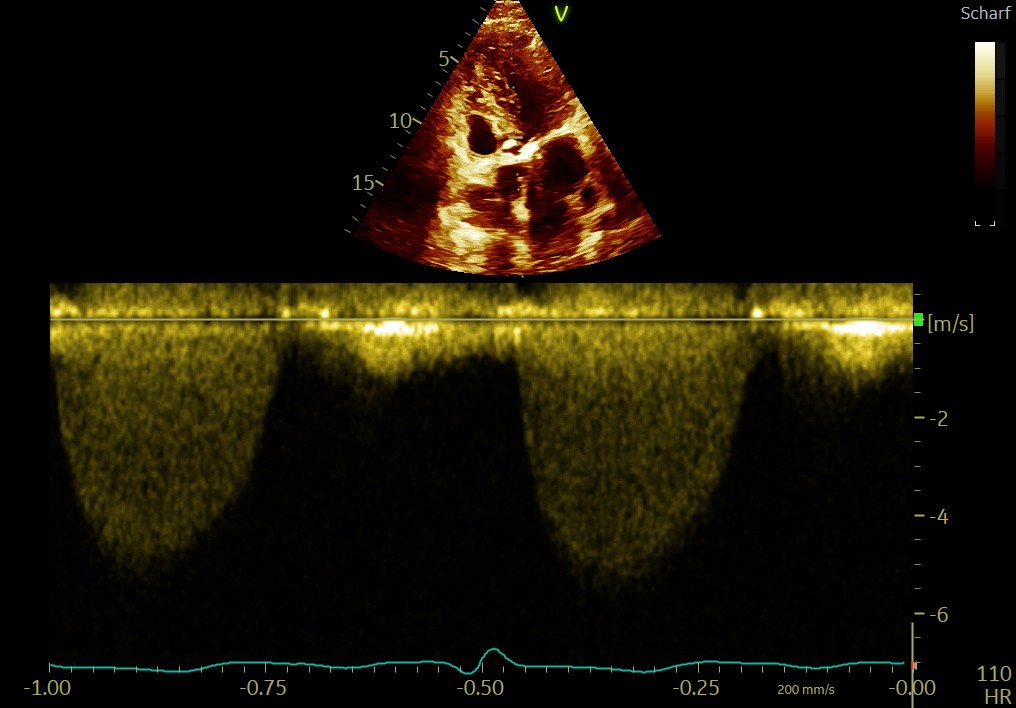

Bicuspid AV with prolapse of the RCC and severe eccentric AR & eccentric LVH ➜ volume overload